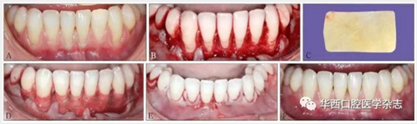

XCM在應(yīng)用初期是用于增加附著齦,后來(lái)發(fā)現(xiàn)對(duì)牙根覆蓋也有很好的效果[10-11]。盡管XCM對(duì)牙根覆蓋的臨床效果不及游離結(jié)締組織,但對(duì)增加軟組織厚度的效果比較肯定[12]。臨床研究[13]證實(shí),XCM適合于軟組織增量手術(shù),并可以代替自體組織(游離結(jié)締組織)增加牙槽嵴的容量和高度。該方法較自體組織手術(shù)疼痛明顯減輕,麻醉藥的使用量減少,患者對(duì)手術(shù)的接受程度增加。具體手術(shù)方法見圖2。

A:下頜從左側(cè)第一前磨牙到右側(cè)第一前磨牙,牙齦廣泛進(jìn)行性退縮,根面敏感,臨床附著水平和附著齦喪失;B:下頜從左側(cè)第一前磨牙到右側(cè)第一前磨牙翻起半厚瓣,常規(guī)根面處理;C:XCM;D:使用5-0可吸收線采用連續(xù)褥式縫合方式將XCM縫合在唇頰側(cè);E:無(wú)張力情況下,使用5-0可吸收線行連續(xù)褥式縫合,將半厚瓣冠向復(fù)位并將XCM完全覆蓋;F:術(shù)后6周,由于牙槽骨吸收,下頜中切牙牙根表面沒(méi)有達(dá)到完全覆蓋,但是角化組織(附著齦)增加了3~4 mm。

圖 2 XCM結(jié)合冠向復(fù)位瓣術(shù)